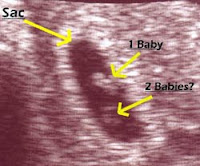

Jika kehamilan tidak terjadi, kadar estrogen dan progesteron menurun. Pada waktu tubuh sudah tak lagi membuat sel telur dan tidak melakukan ovulasi, tubuh juga tidak membuat progesteron. Terjadinya penebalan dinding rahim biasanya cuma bisa diketahui oleh dokter setelah melakukan pemeriksaan ultrasonografi (usg). Penebalan dinding rahim merupakan salah satu faktor penghambat kehamilan untuk wanita. Selain diakibatkan oleh polycystic ovary syndrome (pcos), penebalan dinding rahim juga sangat berpengaruh langsung terhadap wanita menjadi sulit untuk hamil.